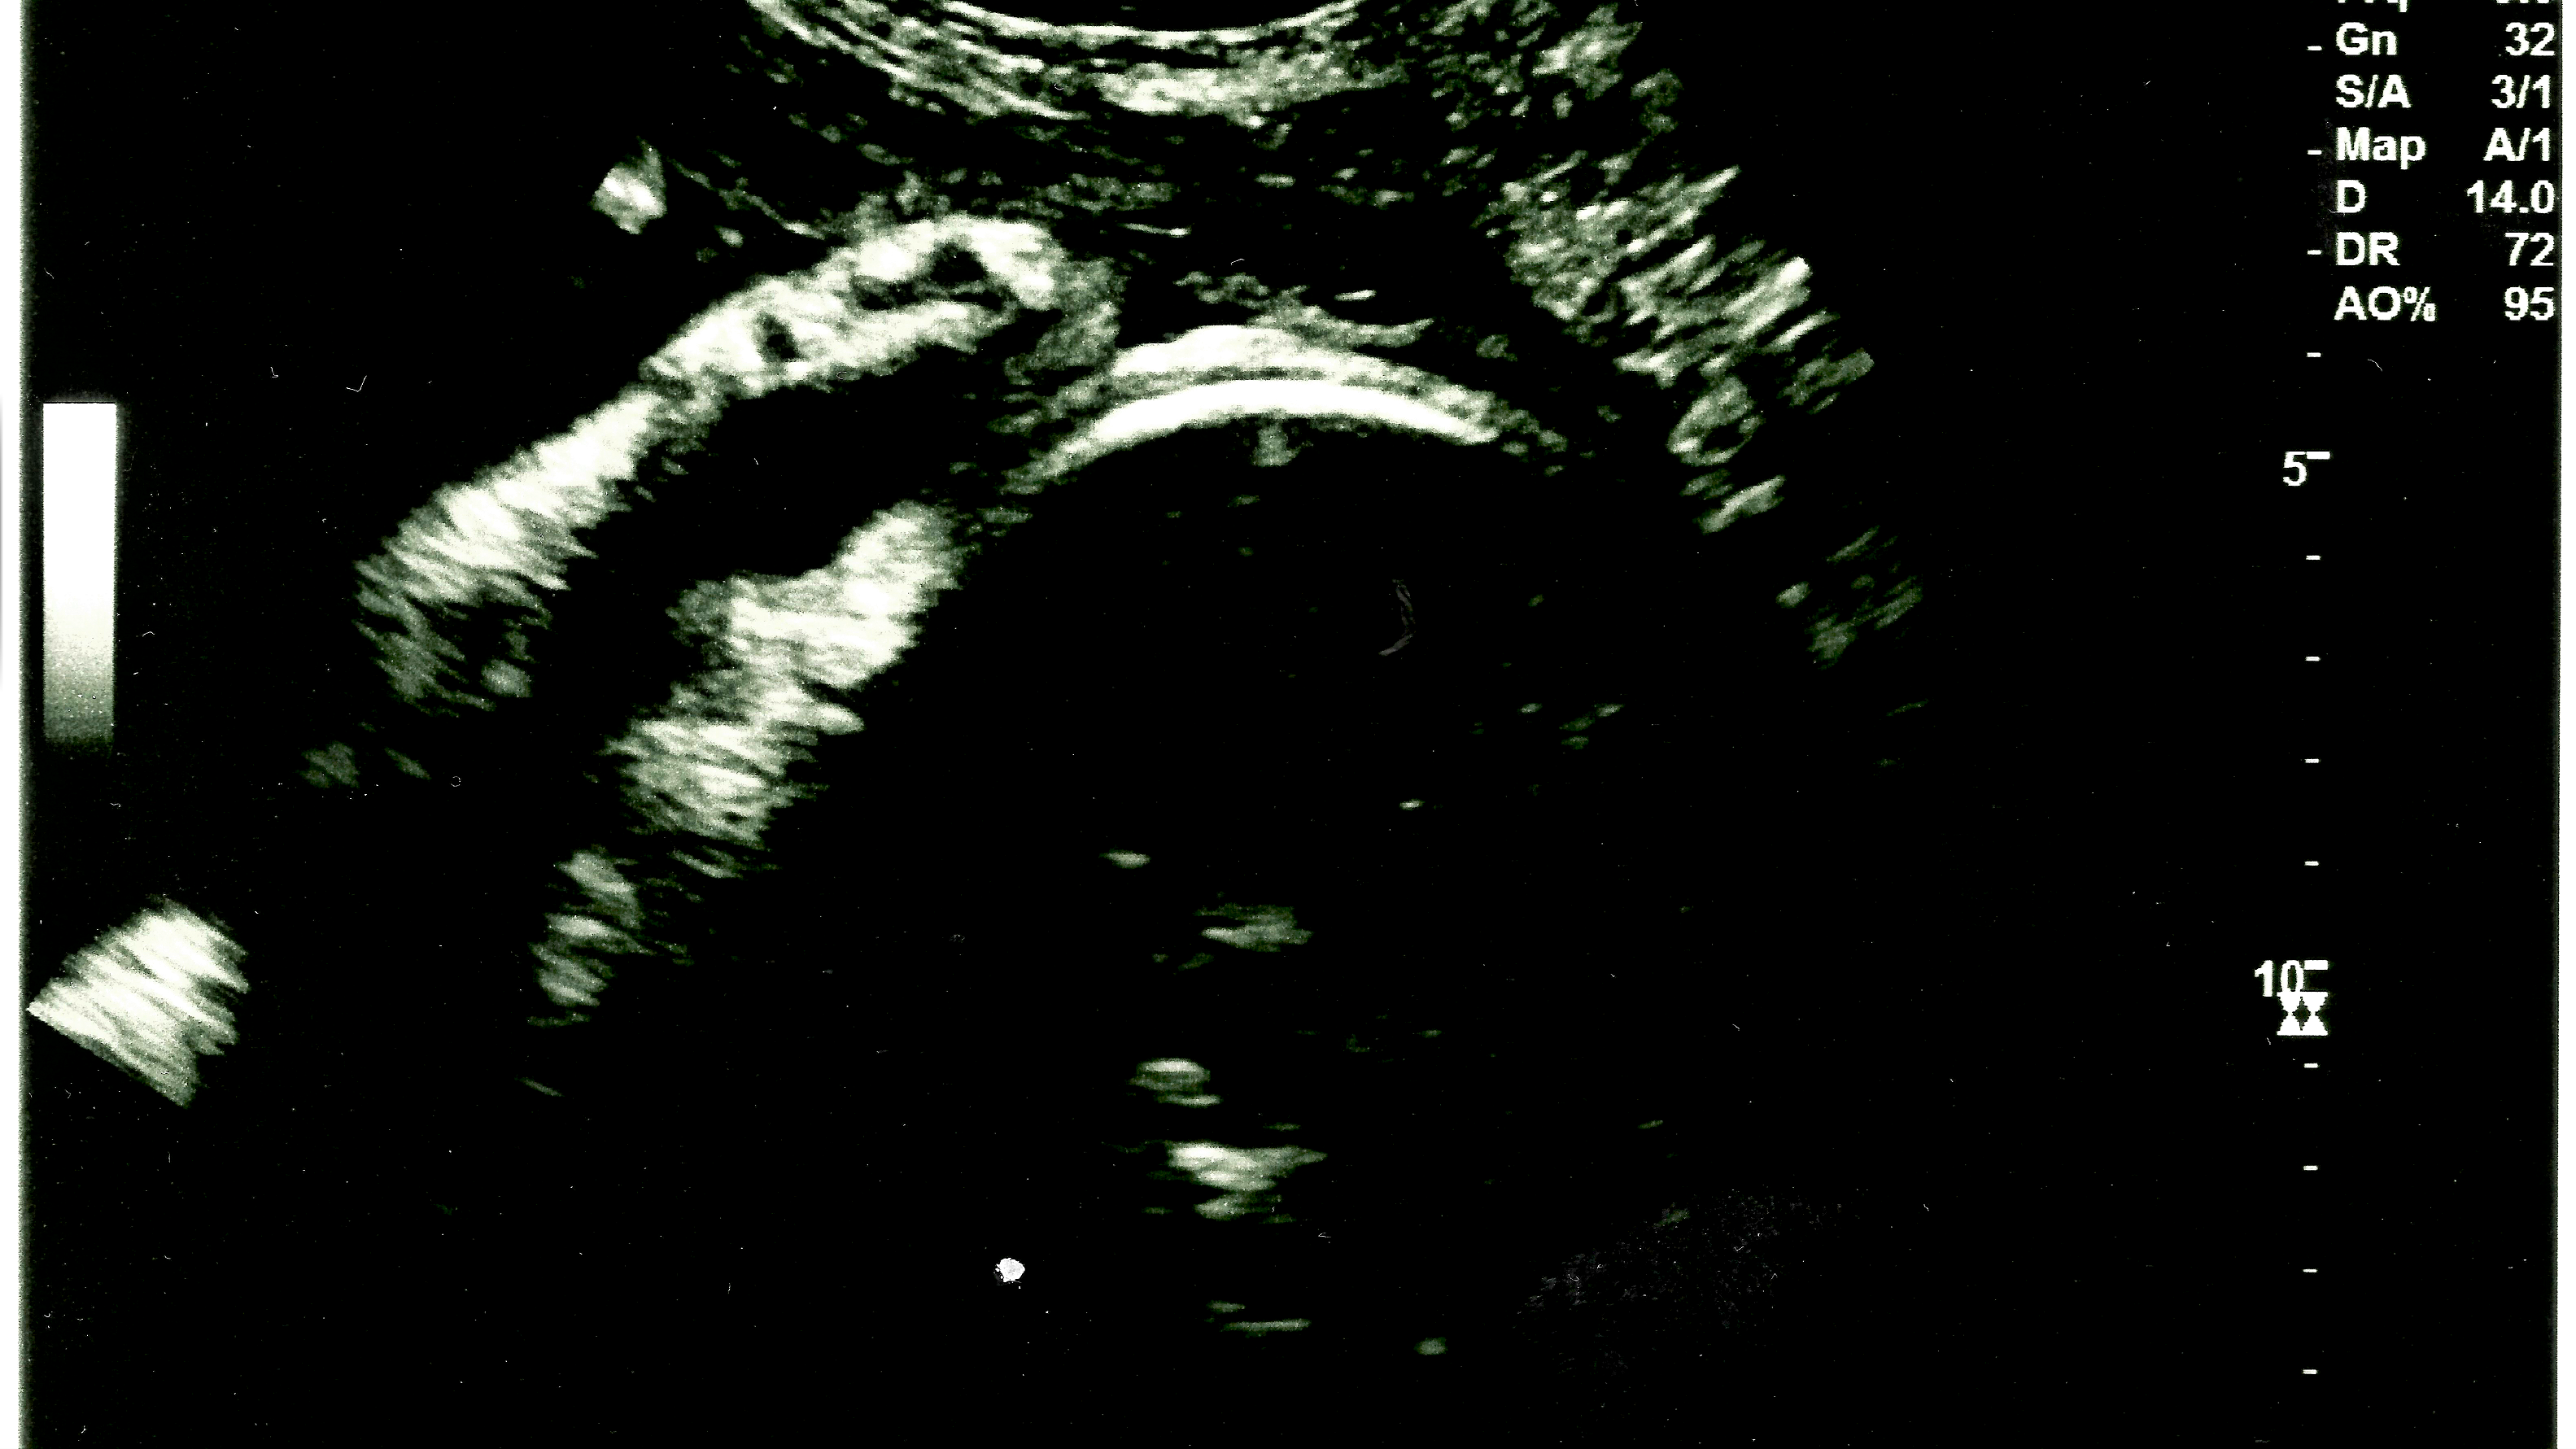

My wife recently had an ultrasound.

We’re due to have another baby soon, but my wife’s measurements gave the doctor cause for concern. So we had an anatomy ultrasound to make sure everything was okay. And of course, everything is okay.

I guess you don’t usually get this ultrasound so late in pregnancy (unless your insurance is awesome I guess), but the baby is larger than expected and they wanted to check. That’s good.

What’s amazing was being able to see his little features through the monitor.

His nose. His lips. His eyes. His puff cheeks.

I was definitely feeling emotional. This little guy is ready and now we wait.